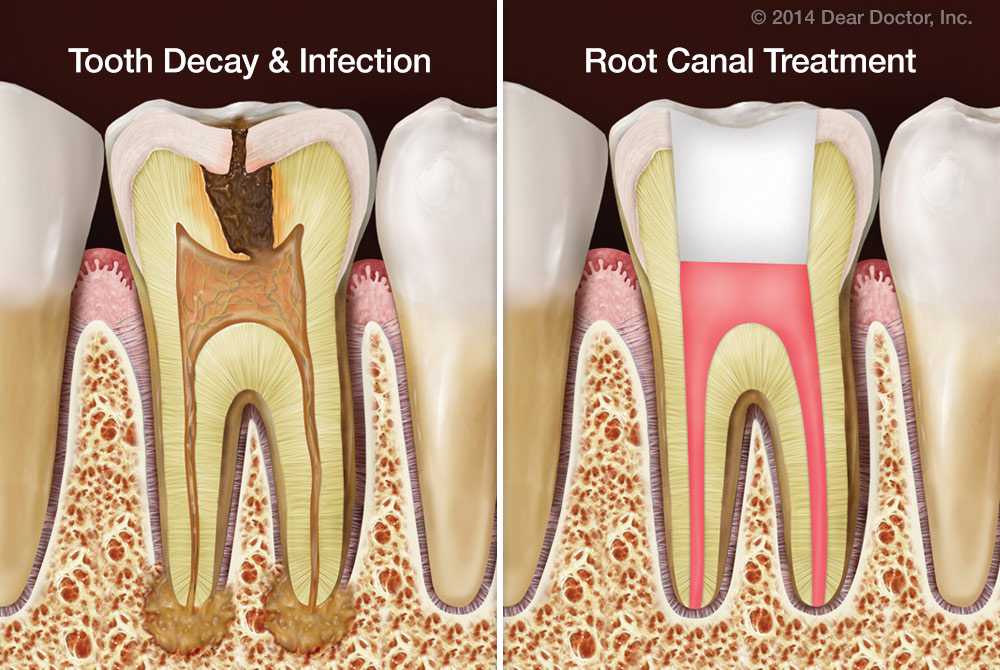

What is root canal treatment?

teeth with an infection due to big cavities. A root canal is a routine dental treatment that can be performed to save your natural tooth while cleaning out damaged or diseased tissue.

Every tooth has pulp — living tissue inside the root that connects it to your bone and gums. The pulp is filled with blood vessels, nerves, and connective tissues. The following situations may result in compromised pulp and roots: 1 teeth that are cracked or chipped 2 teeth that have undergone repeated dental work 3 teeth with an infection due to big cavities

Root canals become necessary when infection or inflammation develops in the soft tissue (pulp) inside and surrounding one of your teeth. Damaged tissue is carefully removed and your tooth is sealed so that new bacteria can’t enter it.

Technically speaking, the root canal itself is a part of your tooth. It is where the blood vessels, connective tissue, and nerves lie, and it extends through the root of the tooth. What we think of as a root canal is actually a root canal treatment, also known as endodontic treatment. It’s a very common procedure, ...

Common causes for root canal infections include: 1 Dental decay (cavities) that spreads beneath the enamel layer and into the pulp chamber. 2 Dental damage, like chips and cracks, that exposes the inner layer of your tooth, allowing harmful bacteria inside. 3 Dental trauma, even if there aren’t visible signs. 4 Repeated dental treatments to a tooth.

The part of the tooth below the gumline is called the root of the tooth. One of the most common reasons a root canal is needed is because of a cavity. There are other reasons, but by in large, the biggest reason is because of cavities.

Now that’s a problem. It’s reached the gateway of the tooth to the rest of the body: the dental pulp. The center of the tooth contains the pulp which is a small canal. The pulp runs along the entire length of the root to the bone.

Why do you put a crown over a tooth?

Where does tooth decay occur?

Sometimes tooth decay gets in the inner layers of a tooth, including the pulp and root. That area is sensitive since it contains a network of blood vessels and nerves. Injury caused by trauma, cracks, and chips in the teeth may contribute to deep decay that requires an intervention like a root canal. During the procedure, a specialist will create ...